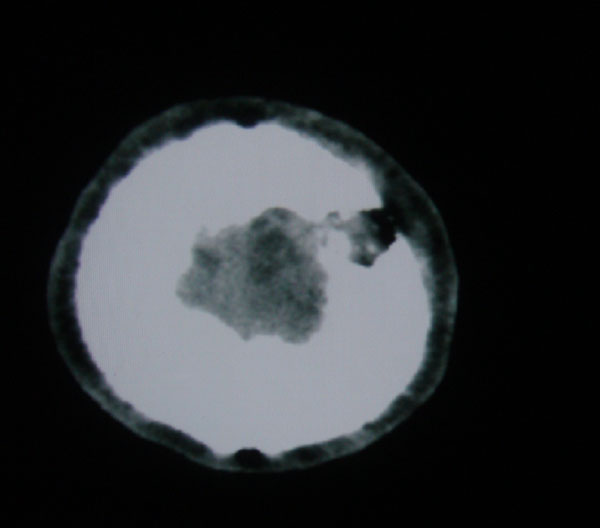

以下是引用拾荒者在2008-6-7 13:05:00的发言:[br]左侧顶骨局限性骨质缺损,边缘锐利,无硬化边,周围软组织轻度肿胀,无明显软组织肿块及骨膜反应,考虑嗜酸性肉芽肿可能。